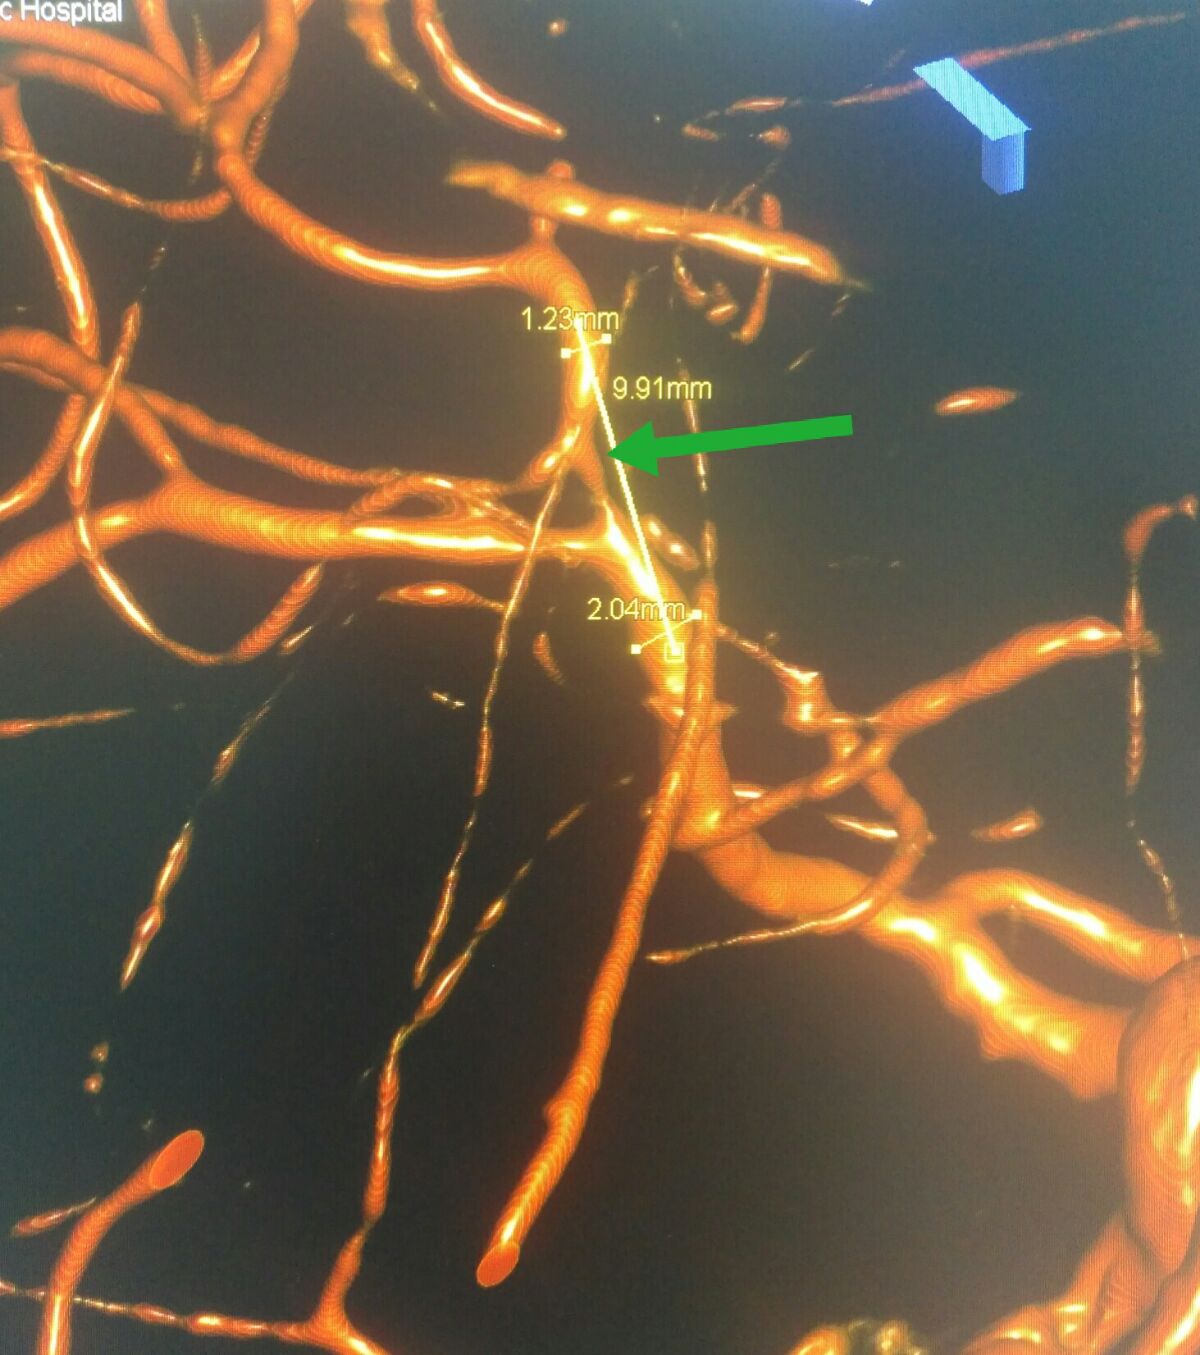

3D处理后可见大脑中动脉下干重度狭窄

3D处理后可见大脑中动脉下干重度狭窄

3D处理后不同角度显示大脑中动脉下干重度狭窄